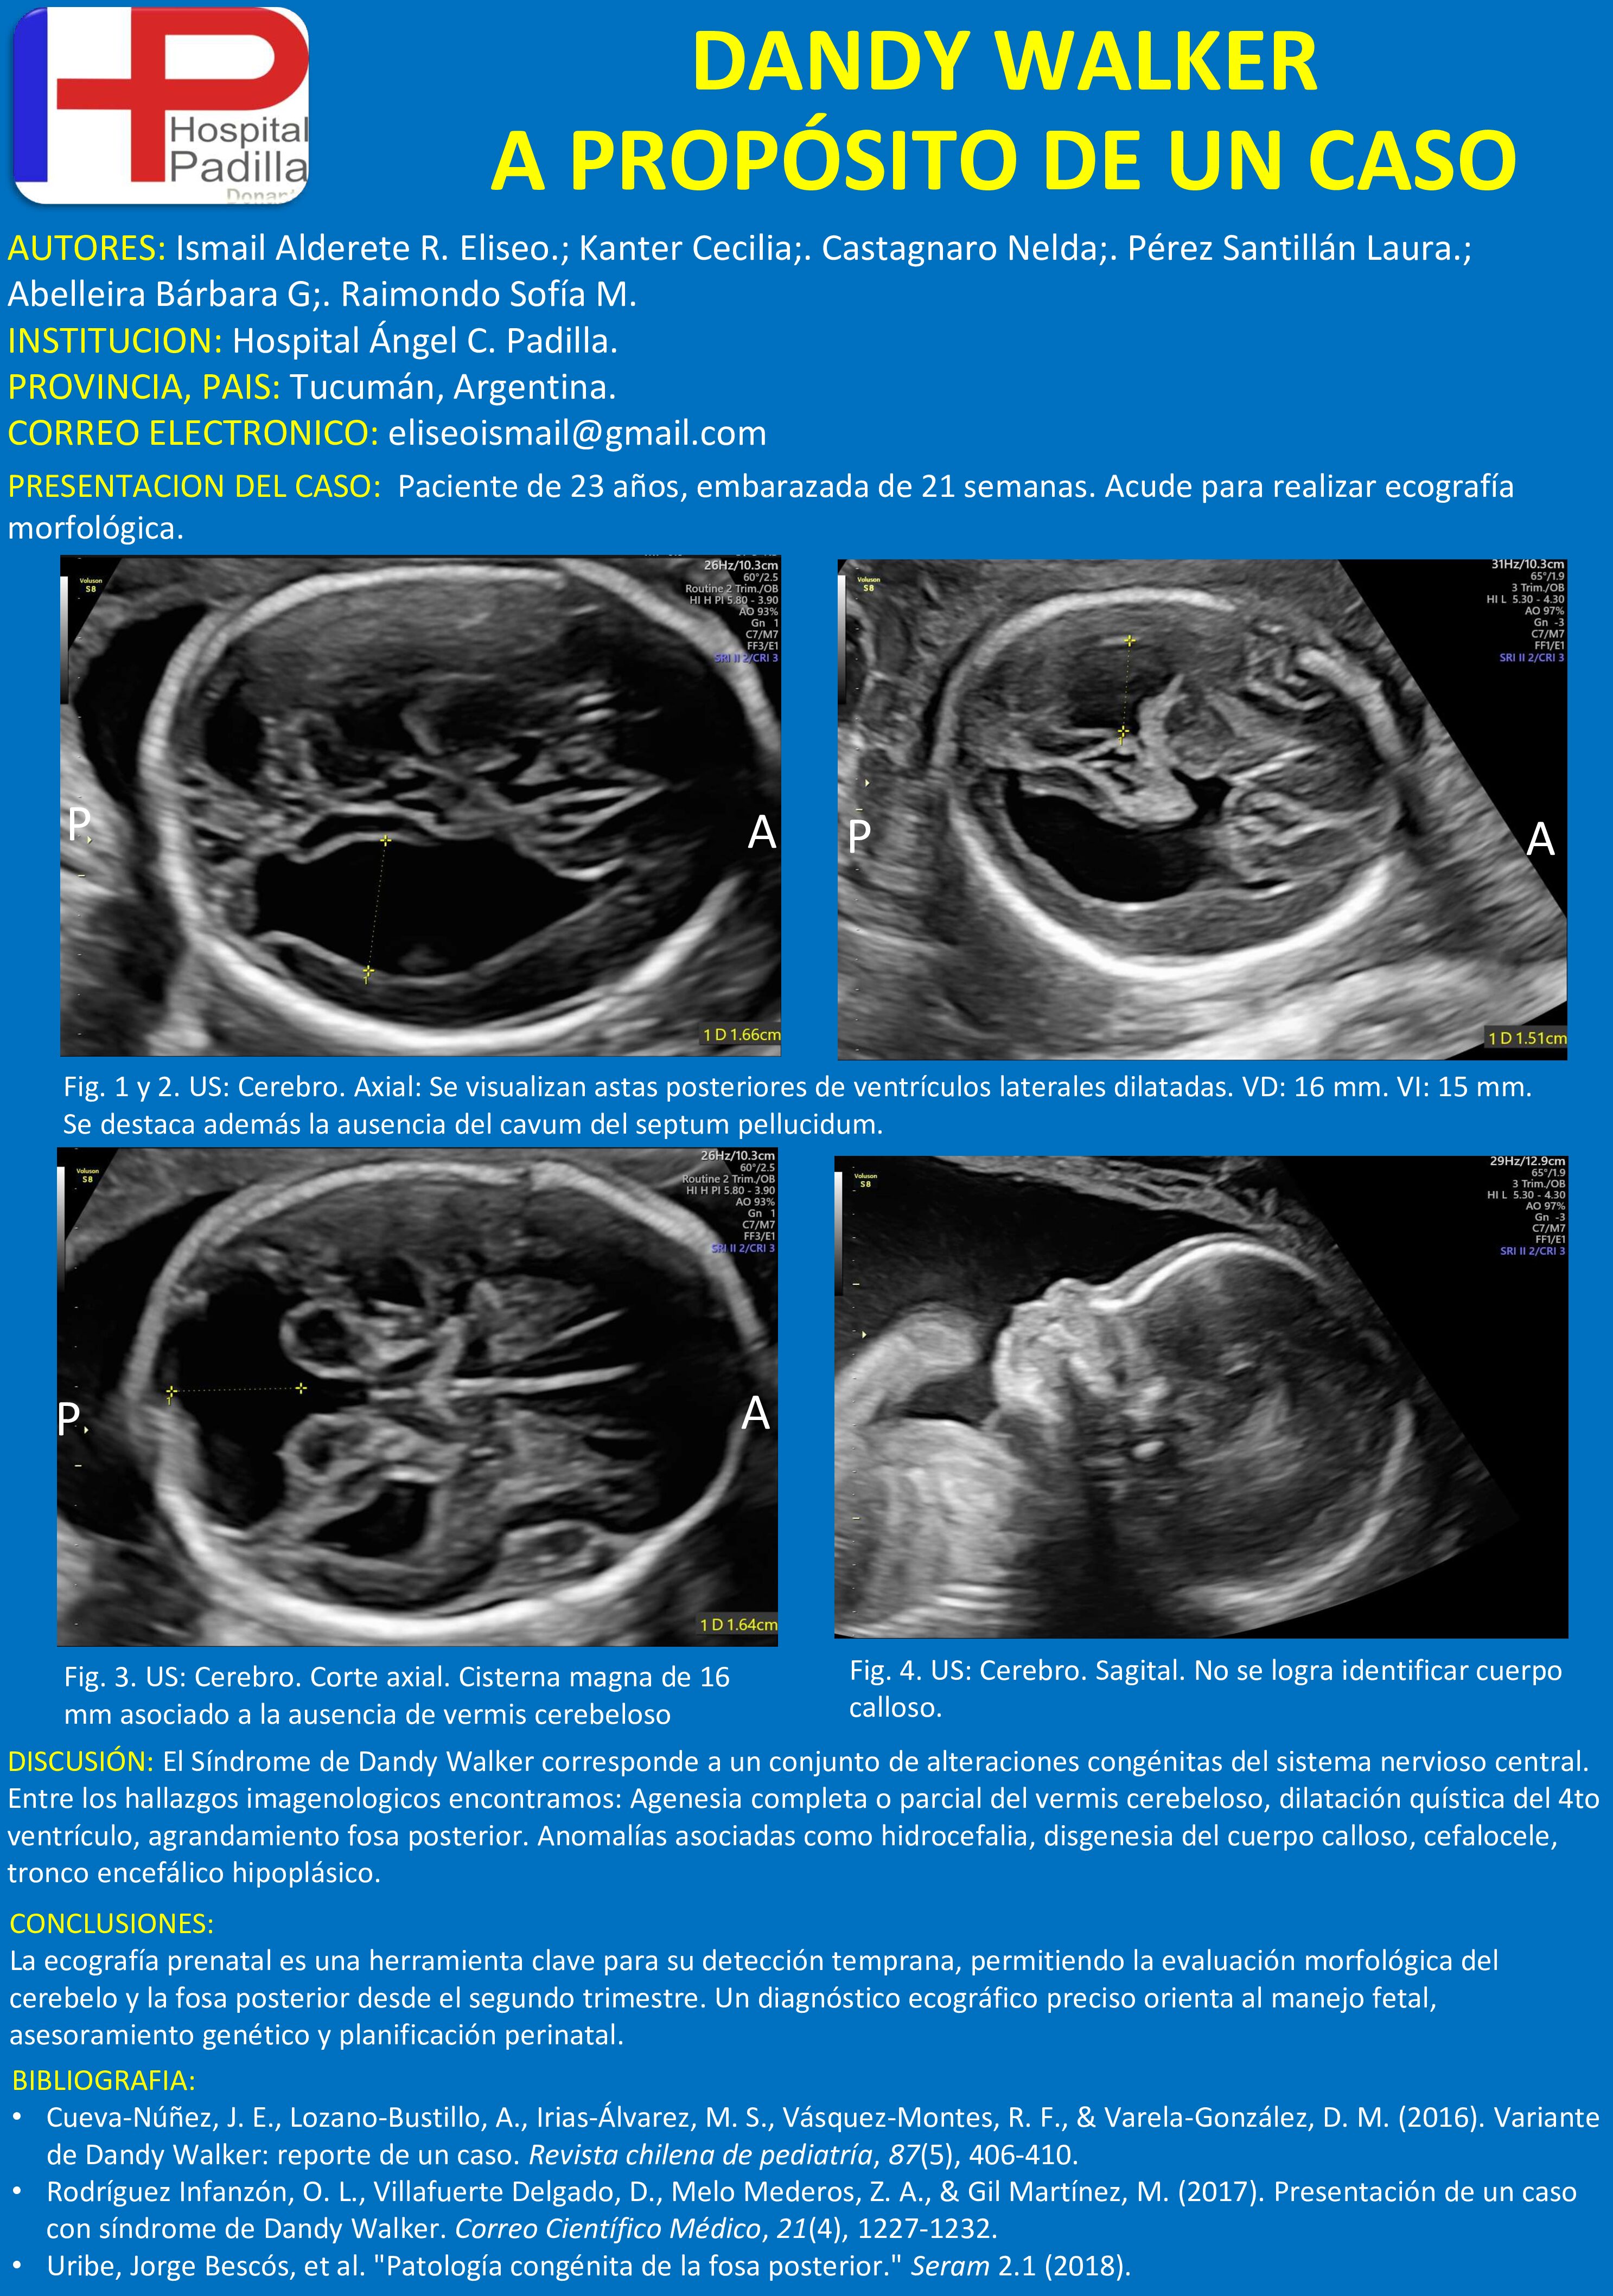

DANDY WALKER A PROPÓSITO DE UN CASO